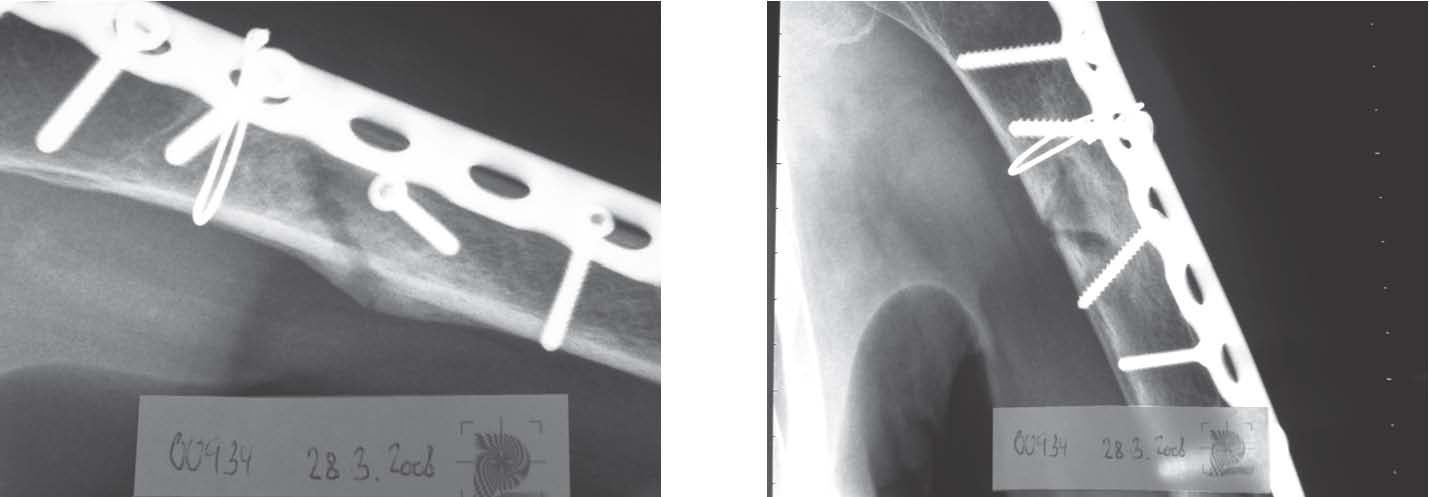

Case 4: Pat No.00934, female, 1938, 15 BICOM® therapy sessions

Patient history, findings and evaluation

On 19.10.2007 the patient stumbled over a root. Diagnosis: Proximal humerus fracture. Osteoporosis The discharge report of 27.10.2007: Wounds continue to heal well without irritation, however there is a clear swelling of the left elbow and left hand.

X-rays of 19.10.2007

X-rays of 23.10.2007(4 days postoperatively)

The discharge report of 27.10.2007: Wounds continue to heal well without irritation, however there is a clear swelling of the left elbow and left hand.

30.10. 2007 (11 days after the accident): Checkup in my practice. Discussion on how to proceed. As I have no Xray facilities in my practice, further checkups to be carried out by the orthopaedic surgeon. Recommendation for vitamin D injections (300,000 IU/ampoule).

30.10 – 10.12.2007 (just under 8 weeks after the accident): 3 injections of Vitamin D. The patient tells my assistant during this period that the orthopaedic specialist is unhappy with the healing process. According to the patient he is considering a reoperation because of delayed fracture healing. At this point a suggestion is made to the patient for BICOM® therapy to be carried out.

From 11.12-19.12.2007 3 BICOM® therapy sessions are carried out (basic program, followup program such as lymph activation and a postoperative program). In addition CTT ampoules from the orthopaedics test set). (Therapy sessions 13) The patient reports less pain, a reduction in swelling and also that she is no longer as tired. She took her planned holiday abroad.

On her return from holiday she reports on 22.1.2008 (12 weeks after the accident) that she had been to see the orthopaedic surgeon and he was happy with how things were progressing. The Xrays show the beginnings of fracture healing.

Xrays of 21.1.2008 (12 weeks after the accident)

Subsequently 3 BICOM® therapy sessions are carried out from 22.1.2008 to 25.2.2008. In addition 2 further ampoules of Vitamin D are applied. (Therapy 46) Another check is carried out on 27.2.2008 (17 weeks postoperatively). The orthopaedist if anything expresses scepticism about the further healing process. The fracture meets the requirements of a “delayed union“.

X-ray pictures of 27.2.2008 (17 weeks after the accident)

In the period from 3.3.2008 to 28.3.2008, 5 more BICOM® therapy sessions take place. In addition, cupping is done once across the reflex zones of the vertebral segments. On 23.3.2008 the patient reports that she is very happy and she now only has slight pain. (Therapy 712)

The orthopaedic followup on 28 March is carried out to the satisfaction of the orthopaedic specialist. The Xray images now show (i.e. five months after the fracture) a clear callus formation.

X-rays of 28.3.2008 (21 days postoperatively)